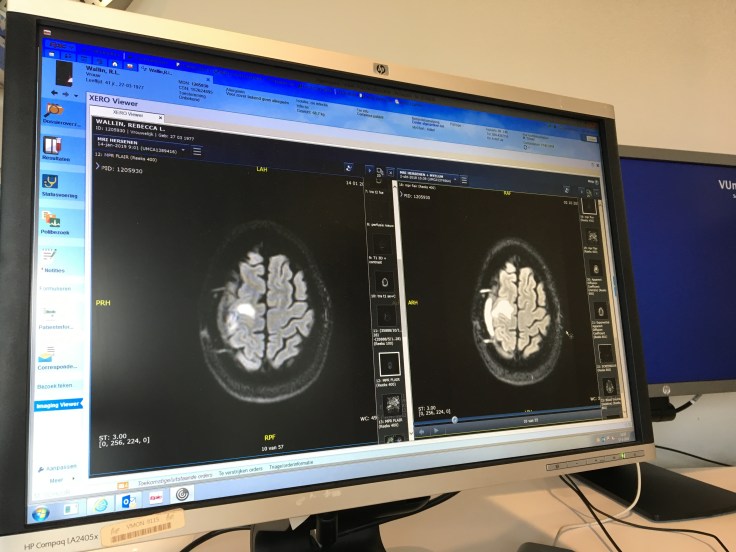

That was week 1. Moving on to week 2; despite having to get to the VU by 08:30 (my body no longer recognises this time of day), despite getting on the ‘direct’ tram (only to find it was on a detour route past the Olympic Stadium), and despite not then having time to grab a coffee before my MRI, I still rock up to hospital on 14th January with a spring in my step.

I’ve had so many scans now, I’m becoming a bit complacent… Would you put all your metal objects into this dish please…sure. Could you climb onto the bed with your head in this cradle… yep. Lift your knees… they’re up. We’re going to put in an IV for the contrast fluid… I hate this bit, but yep, go for it. The earplugs go in, the headphones go on, the protective frame is placed over my face, the panic button is placed in my hand, and I slide off into the machine, as the radiologists take cover in the control room and start talking to me through the headphones…

Having completed the MRI scan and made my way home, I then had a week to wait before seeing my Neurologist for the results. However, the following day I got a routine notification to tell me my medical file had been updated and my results were now available in my dossier online.

Well of course I looked, wouldn’t you? I know the results need explanation and context, and I know they’re in Dutch, but I still had to look.

Of course, I immediately wished I hadn’t, as my Google Chrome browser automatically tried to translate the Dutch report into English. Seeing phrases like “Question: Residual edema? Possible new lesions?” I started to think (always dangerous with Dr Google), and the excitement of being on the home straight suddenly evaporated. If I had more edema or lesions in my head, the last thing they should do is knock out my immune system with more chemo, they’ll be wanting to get me back into neurosurgery…

I emailed my Neurologist and asked for Monday’s appointment to be brought forward. It was, and I saw Dr Schuur on Thursday instead.

The results are good

So it turns out Google’s translation was correct, but the ‘question’ was not a concern from the new scan; but an outstanding question from the old scan, which my Neurologist was asking the Radiologist to rule out. Which he did.

So my Neurologist is happy that there are no new lesions, and the residual edema is to be expected and nothing to be concerned about. She did a physical examination (the usual tests of strength and coordination) and finished off by saying I’m better than when she last saw me, the scan looks good, and she’s happy I’m fit to drive. Get in!